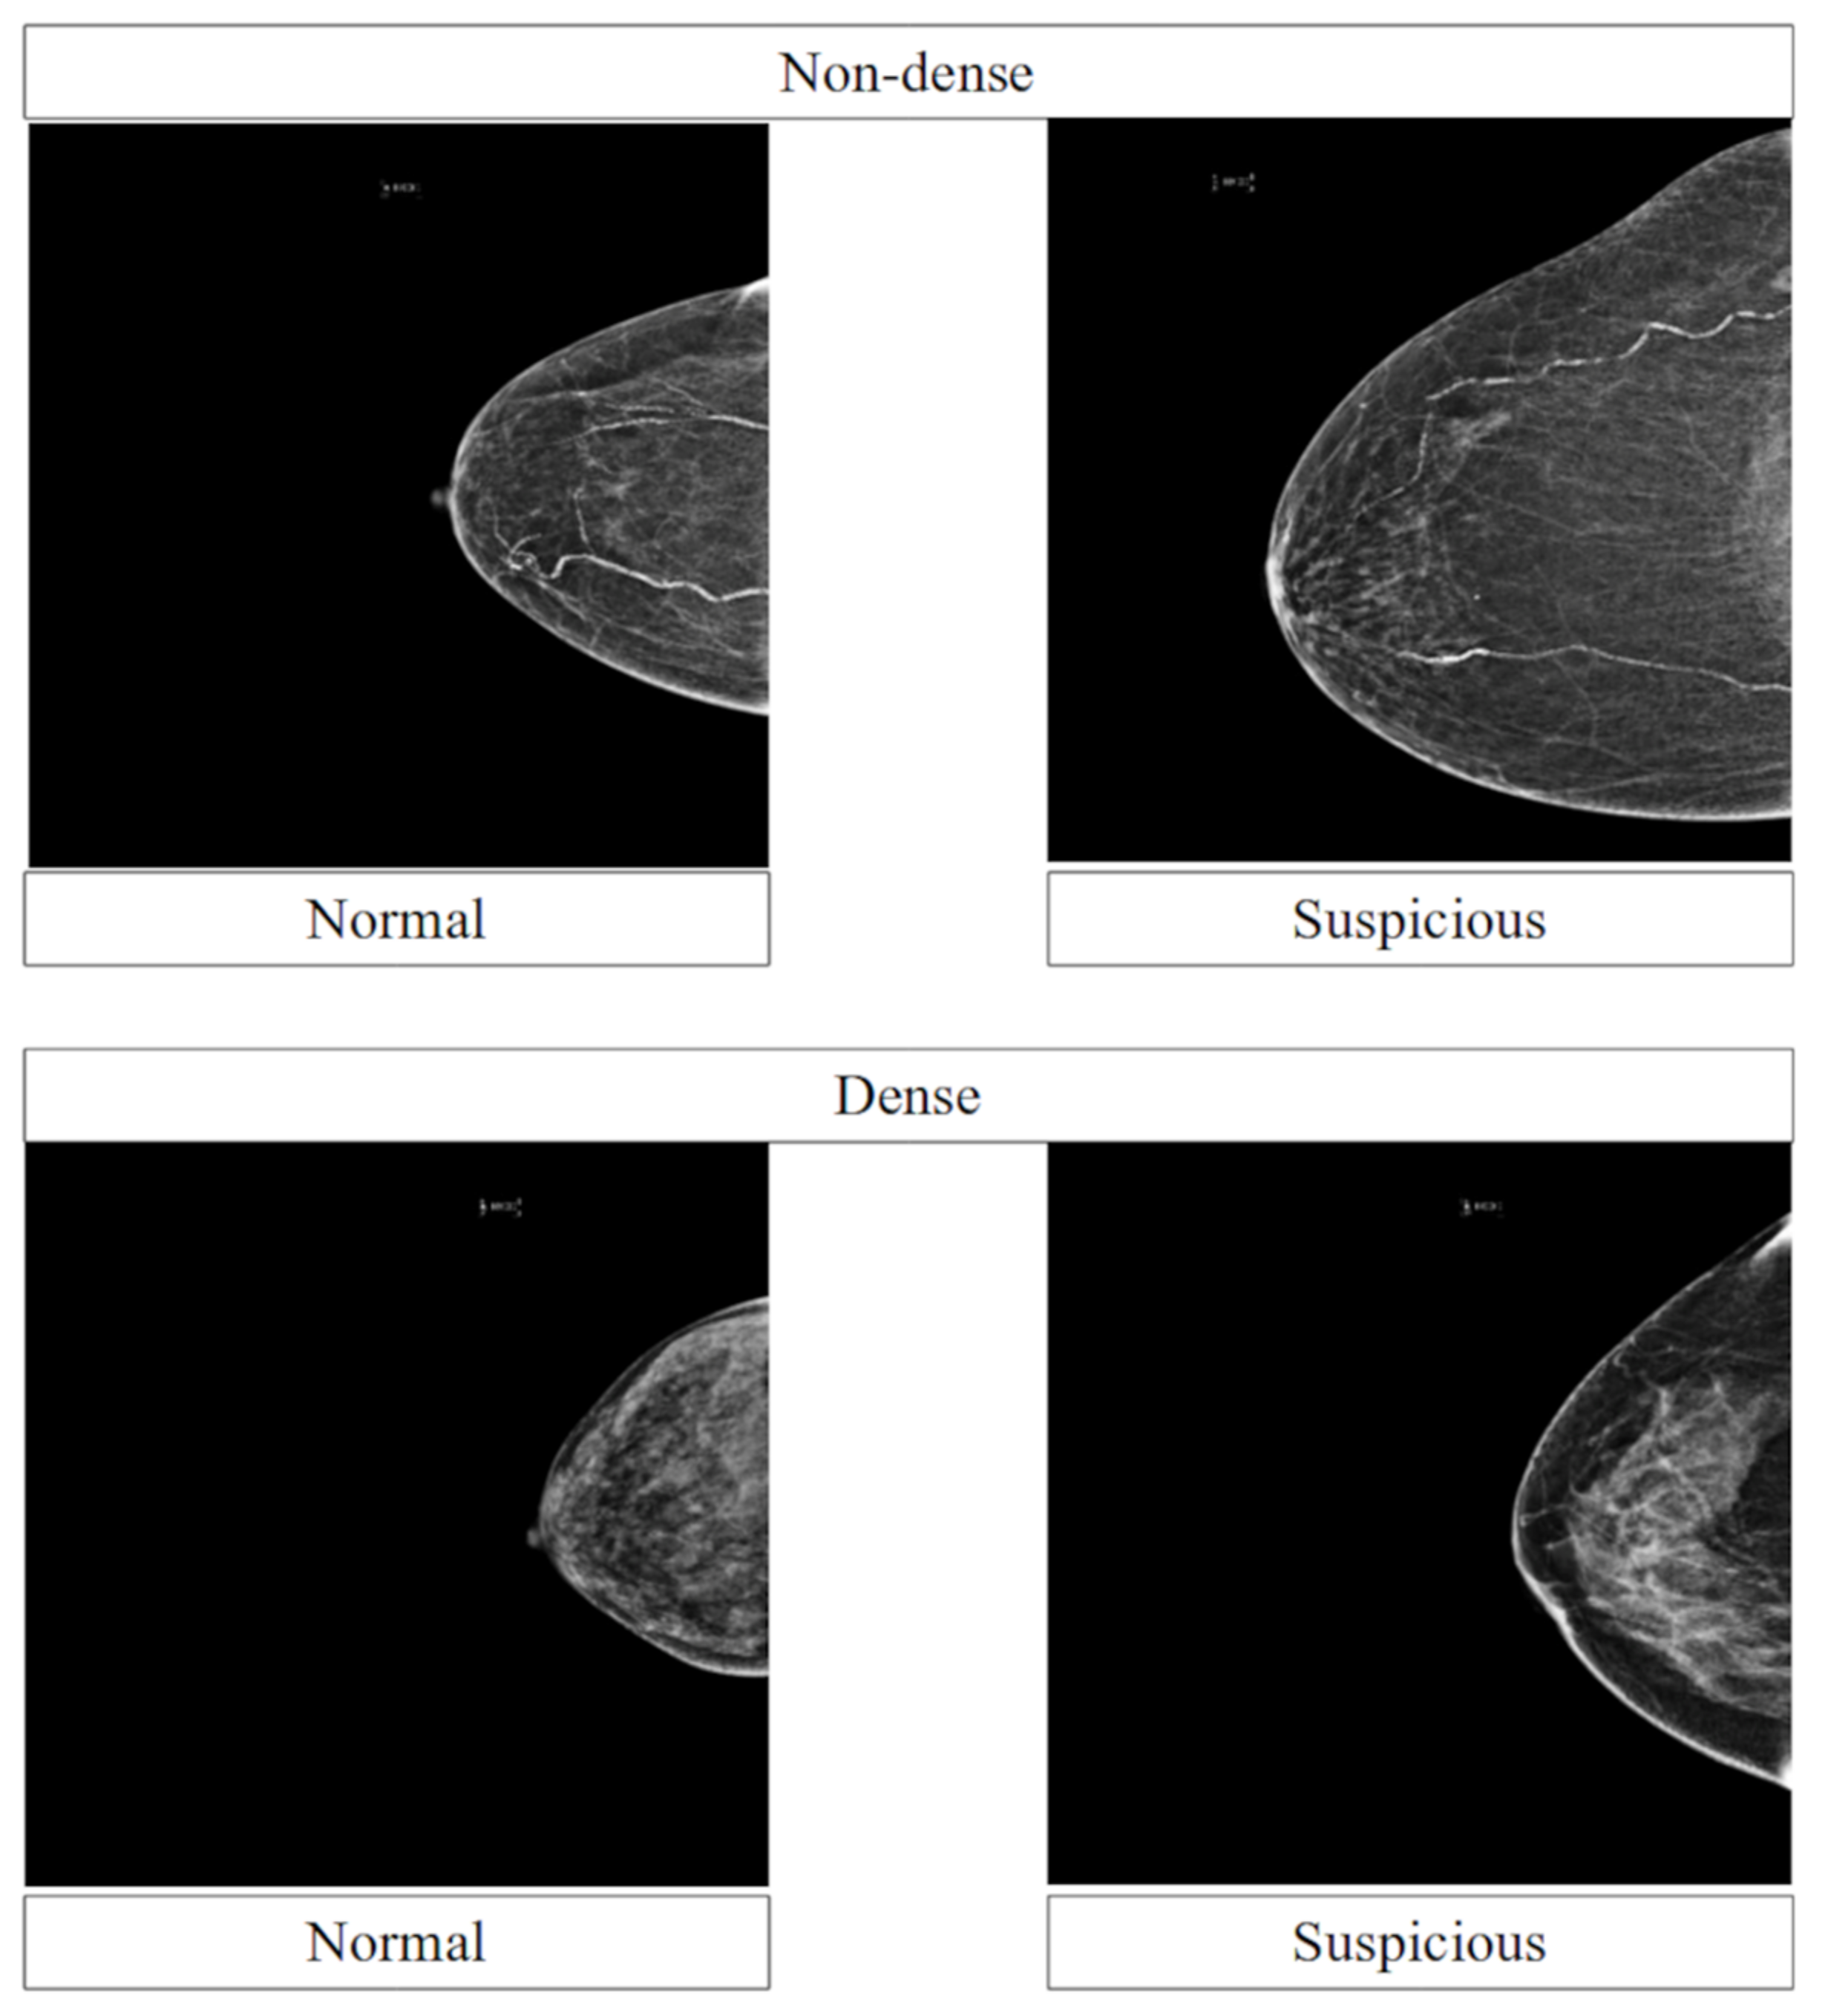

3.6. Performance across Breast Densities

4.3. Performance across Breast Densities